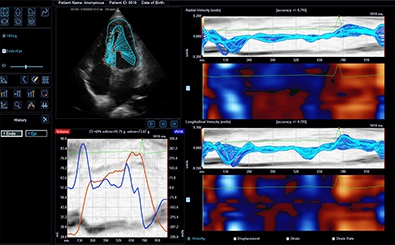

CUBE Strain